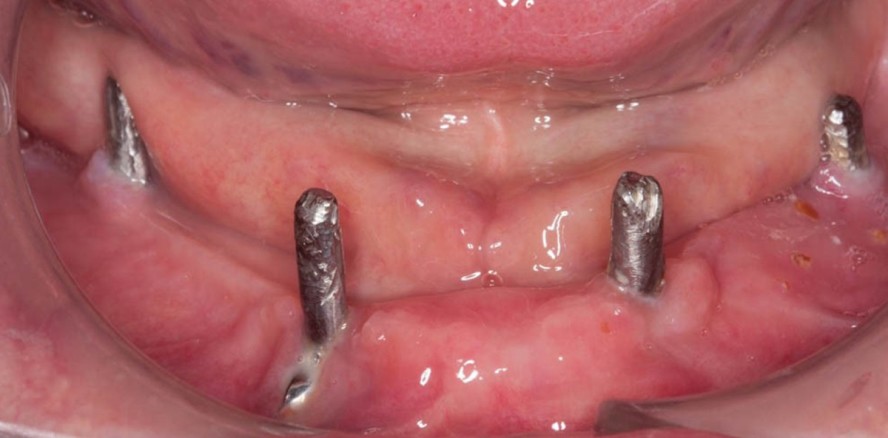

Patient über 80 Jahre mit Periimplan­-titis sowie unzureichender prothetischer Versorgung im Ober- als auch Unter­kiefer. Die Implantate im Oberkiefer tragen nicht zum Prothesenhalt bei. Das Konzept der Protektion für den Pfeilerbestand durch strategische In­sertion von Pfeilerimplantaten zur Vergrößerung des Unterstützungsfelds im Oberkiefer wurde für die be­stehende Prothese missinterpretiert (Kaufmann et al. 2009). Die Oberkieferimplantate weisen eine Periim­plantitis mit Pusaustritt auf. Eine Explantation wird auch ob des redu­zierten Allgemeinzustands seitens des Patienten abgelehnt. Aufgrund mangelnder Com­pliance war eine adä­quate Therapie nicht durchführ­bar. Der Pa­tient kommt in unregelmäßigen Ab­ständen bei wiederauftretenden akuten Beschwerden.